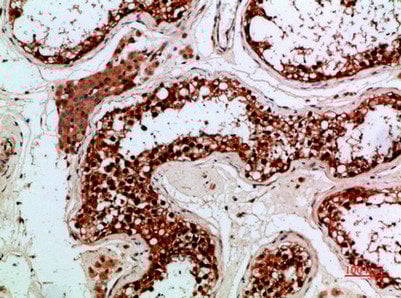

(Immunohistochemical analysis of paraffin-embedded human-testis, antibody was diluted at 1:200)